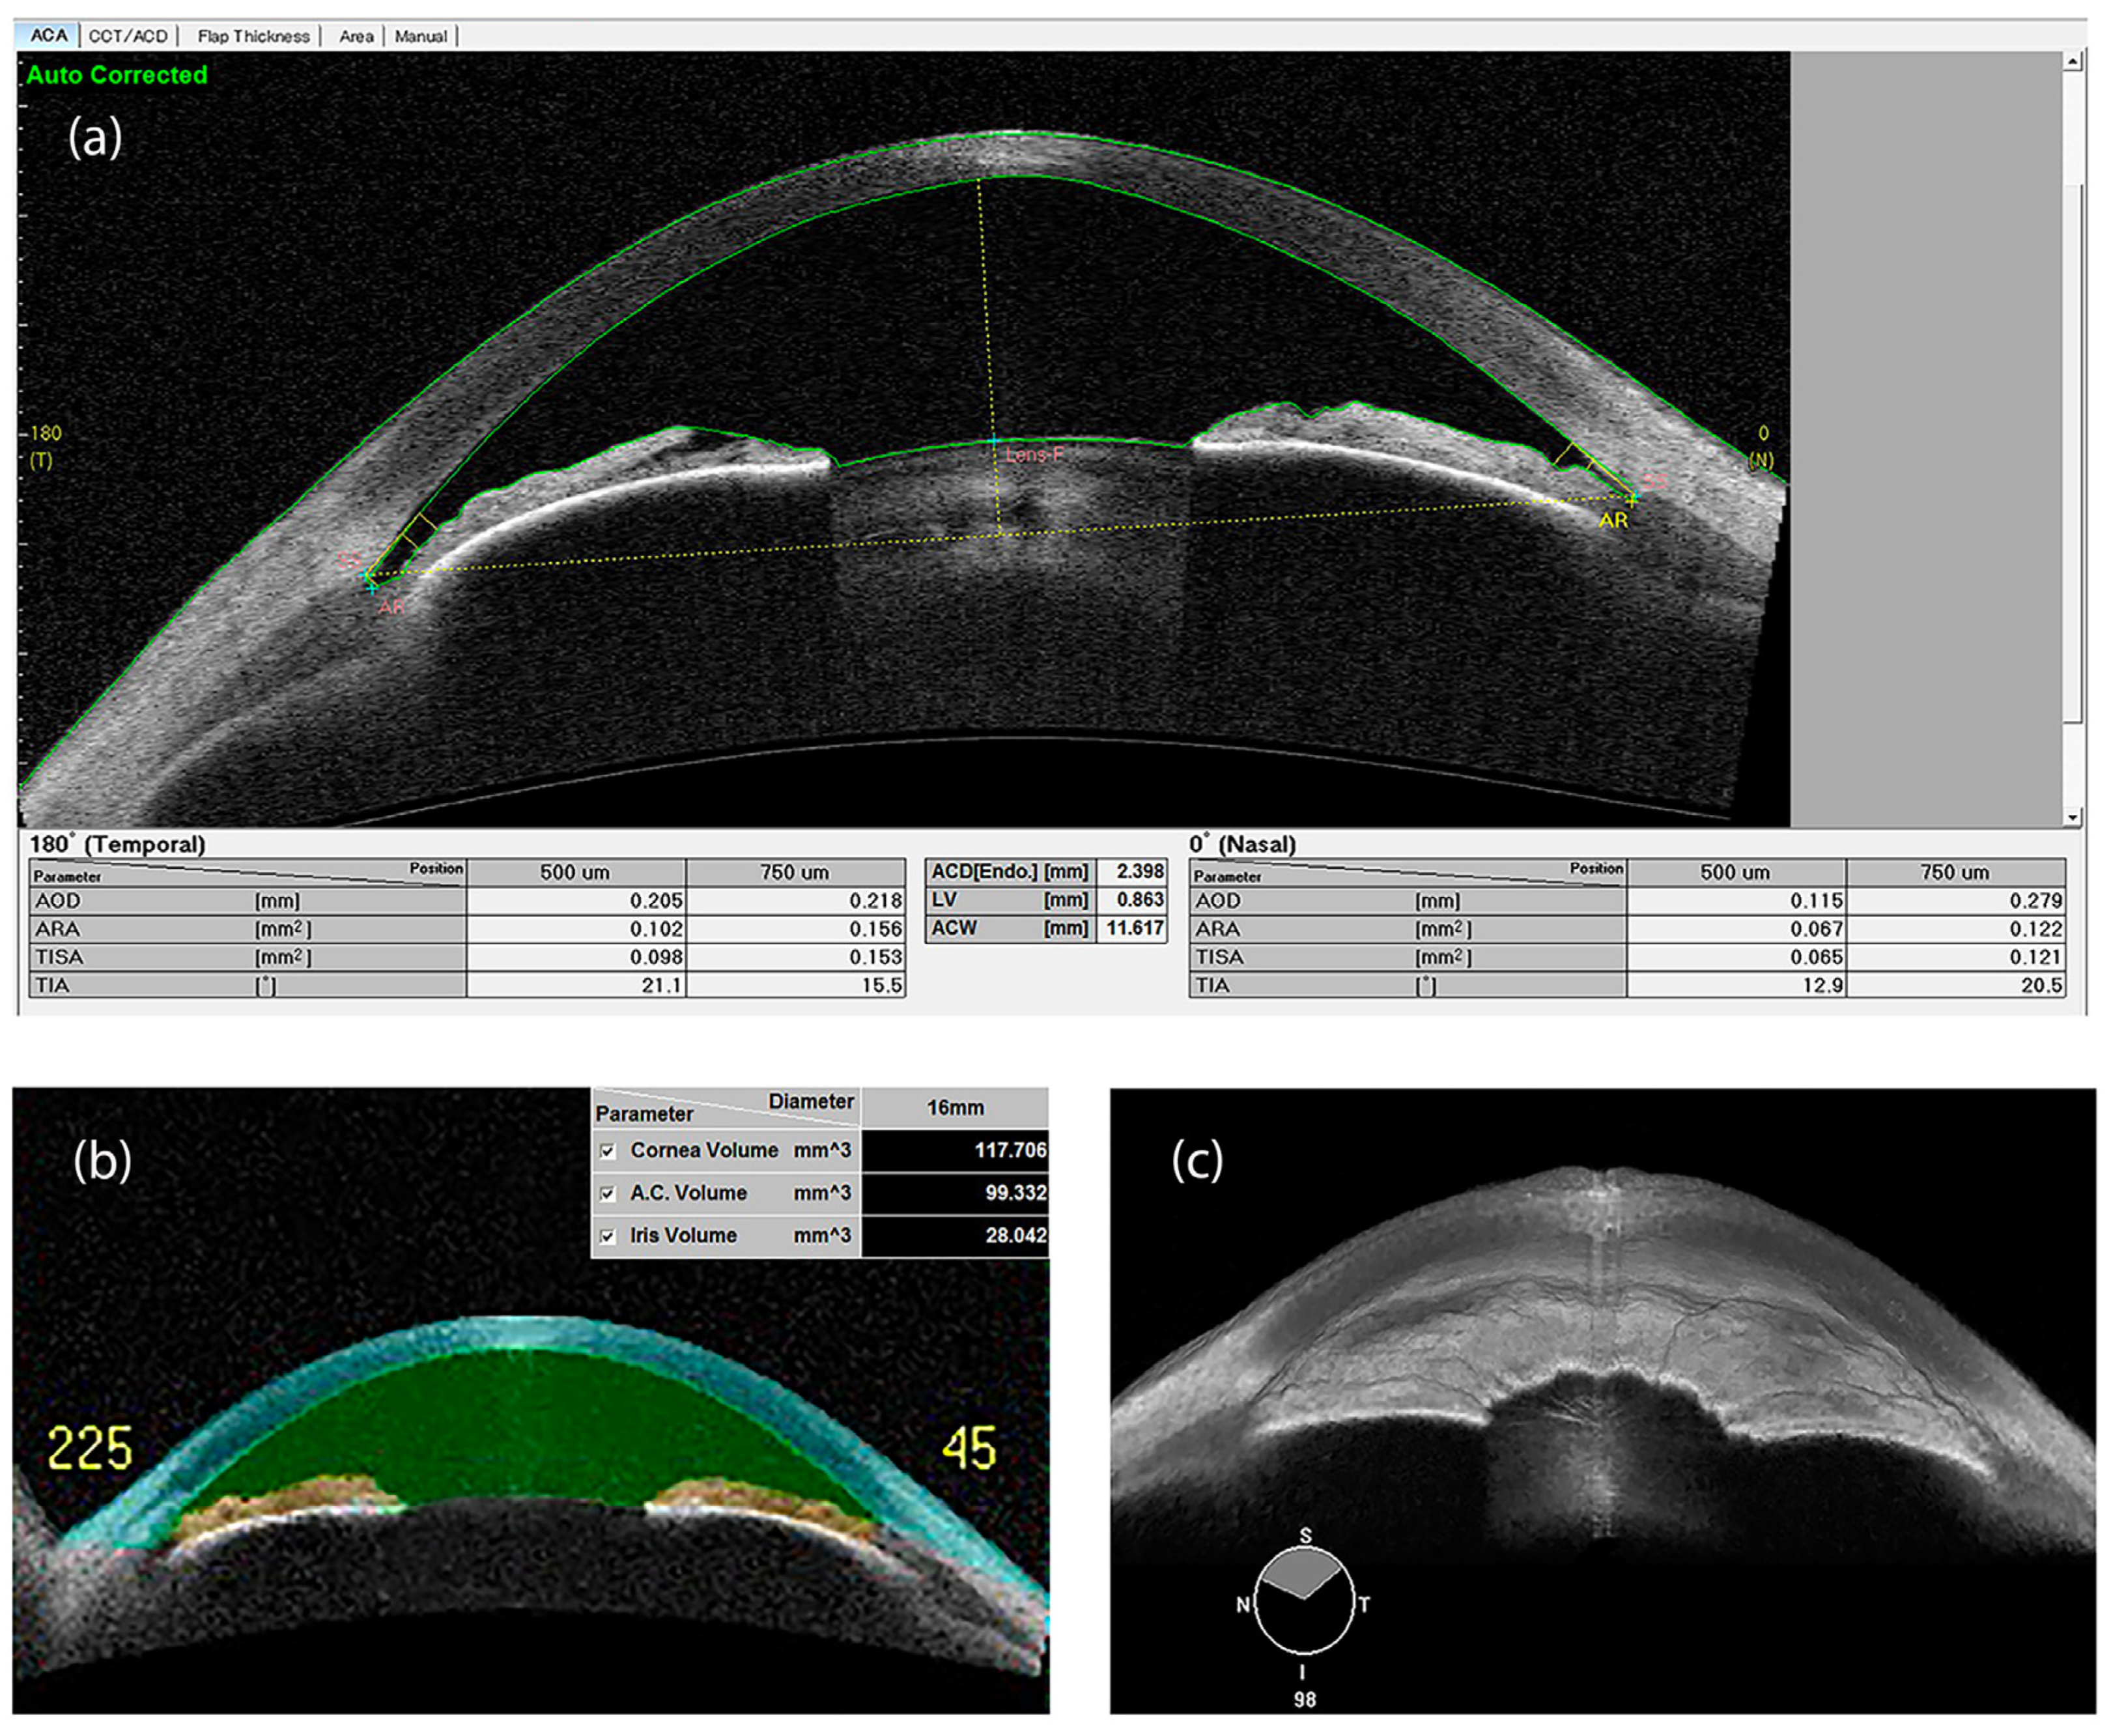

3.4. Anterior Segment Optical Coherence Tomography (AS-OCT)

| Angle opening distance (AOD) | Distance between the trabecular meshwork and the iris at 500 (AOD 500) or 750 μm (AOD 750), anteriorly to the scleral spur | UBM/OCT |

| Angle recess area (ARA) | The triangular area (ARA 500 or 750) bounded by the AOD 500 or 750, the anterior iris surface and the inner corneo-scleral wall | OCT |

| Iris thickness (IT) | Iris thickness measured at 750 um (IT 750) or 2000 μm (IT2000) from the scleral spur | OCT |

| Lens vault (LV) | The perpendicular distance between the anterior pole of the lens and the horizontal line joining the 2 scleral spurs on horizontal AS-OCT scans | OCT |

| Trabecular iris space area (TISA) | Trapezoidal area (TISA 500 or 750) bounded by the AOD 500 or 750, the anterior iris surface and the inner corneo-scleral wall | OCT |